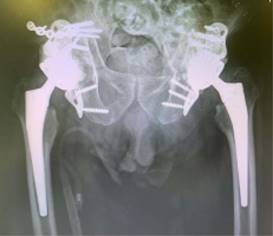

De primera instancia, se llevó a cabo la cirugía de la hemipelvis izquierda dado que a nivel radiográfico presentaba mayor protrusión pélvica y no era deseable que un hematoma en fase de callo blando pudiera generar complicaciones al momento de la extracción de la cabeza femoral (lesiones vasculares, sangrado intraoperatorio). Se retiró la tracción supracondílea. Se colocó al paciente en decúbito lateral derecho, realizándose abordaje posterolateral de Moore con colocación de autoinjerto de la cabeza femoral en el trasfondo acetabular (foco de fractura). Seguidamente, implantación de anillo antiprotrusivo (Burch SchneiderTM Reinforcement Cage, Zimmer Biomet) anclado a isquion e ilion (Figura 2). Previa implantación del anillo, se requirió realizar disección de musculatura glútea (glúteo menor y medio) para alojar correctamente la pestaña superior ilíaca del anillo mediante tornillos corticales. La pestaña medial isquiática del anillo también se ancló mediante tornillos. Se realizó comprobación bajo control de escopía de correcta implantación. Posteriormente, se insertó cotilo de doble movilidad cementado al anillo antiprotrusivo y después se llevó a cabo la implantación del vástago femoral no cementado. Tras finalizar la colocación de los componentes, se procedió al cierre capsular y de musculatura pelvitrocantérica mediante puntos transóseos trocantéricos.

La cirugía de la hemipelvis derecha se llevó a cabo siete días después de la primera. Se colocó al paciente en decúbito lateral izquierdo. Para abordar la fractura longitudinal de pala ilíaca se realizó la primera ventana lateral del abordaje ilioinguinal. Se sintetizó con placa anatómica de seis agujeros. Posteriormente, se realizó el mismo procedimiento que la cirugía previa, usando anillo antiprotrusivo con cotilo de doble movilidad cementado y vástago femoral no cementado.

Durante el seguimiento del paciente, a los 12 meses de la intervención ya realizaba carga completa con la ayuda de un bastón, con una puntuación de Harris hip score (HHS) de 79 en cadera izquierda y 77 en cadera derecha; y una puntuación de 12 en la escala de WOMAC. No ha presentado ninguna complicación postoperatoria hasta el momento (Figura 2). El paciente clínicamente se encuentra satisfecho, refiere molestias ocasionales y una leve cojera de predominio derecho. Presenta balance articular completo a la exploración y no refiere haber tenido ningún episodio de inestabilidad desde la cirugía.